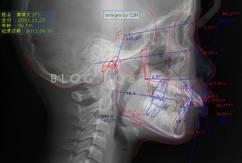

談到早期矯正,涉及到對(duì)雙期矯正概念的理解、適應(yīng)癥的把控、各種早期矯正裝置的制作與安裝、患者生長(zhǎng)發(fā)育知識(shí)的了解等內(nèi)容。

下面這個(gè)小患者就存在需早期矯正的問題。通過早期矯正,在不長(zhǎng)的時(shí)間內(nèi)就達(dá)到極為明顯的療效。她的情況如果等到牙齒替換完畢后再解決,矯治的難度則會(huì)非常大。